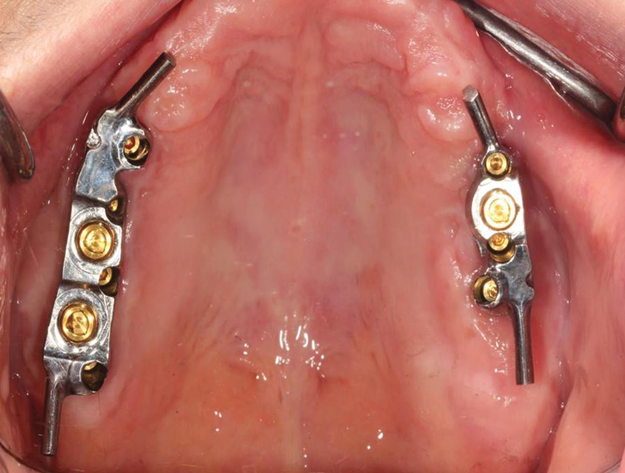

Diverse situații clinice pot fi avantajoase pentru fabricarea unei supraproteze cu bară, inclusiv: când există pierderi excesive de țesuturi moi și dure; când implanturile nu pot fi plasate relativ paralele între ele (fig. 5); când implanturile nu pot fi inserate în locații ideale datorită prezenței structurilor anatomice, distribuției A-P slabe, maxilarului în formă de U sau ocluziei de clasa III; sau atunci când există o discrepanță verticală sau orizontală mare între crestele maxilare și mandibulare.41 Pacienții sensibili la flanșele voluminoase ale unei proteze pot beneficia, de asemenea, de o supraproteză cu bară, deoarece permite reducerea acestora. Cu toate acestea, trebuie remarcat faptul că o supraproteză cu bară este, în general, mai costisitoare decât cea cu un design neconsolidat și mult mai dificil de adaptat ulterior la o proteză existentă.

În ceea ce privește paralelismul implanturilor neconsolidate, acestea trebuie inserate cât mai paralel posibil pentru a evita uzura elementelor retentive; acest lucru este mai puțin important în cazul conceptelor consolidate, deoarece o bară de substructură poate găzdui implanturi neparalele. În cazul designului neconsolidat, nu există o recomandare precisă cu privire la distanța minimă sau maximă între implanturi, dar în cazul celor care retenționează o bară, se impun 10 mm între centrele implanturilor pentru a găzdui elementele de retenție (fig. 8). De exemplu, clemele Hader și cele mai multe elemente de retenție necesită spațiu de 5 mm și câte 2,5 mm pentru titan pe fiecare parte.23